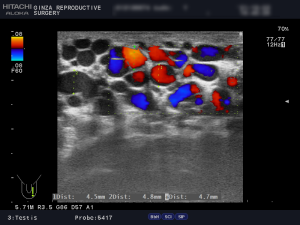

陰嚢のエコー検査の画像と解説

(例)左側2画面のエコー検査の画像です。

左の静脈径は、6.8mm 6.2mm 4.5mm 4.8mm 4.7mm。

ドップラで安静でも逆流著明、腹圧でさらに増強していました。

以上の所見より、診断は左側グレード3の精索静脈瘤です。